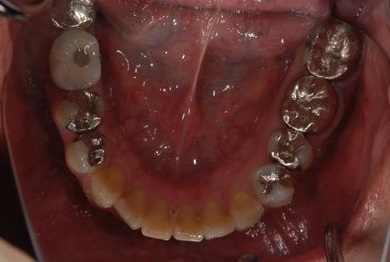

| 性別/年齢 | 女性 / 46歳 | ||||||||||||||||||||||||||||||||

| 主訴 | 歯ぐきがただれてる。歯が少しうずく。 | ||||||||||||||||||||||||||||||||

| 治療方針 | インプラント治療にて、機能的・審美的回復を行う。 | ||||||||||||||||||||||||||||||||

| 治療内容 | インプラント1本(GBR)、ハイブリッドセラミック1本 | ||||||||||||||||||||||||||||||||